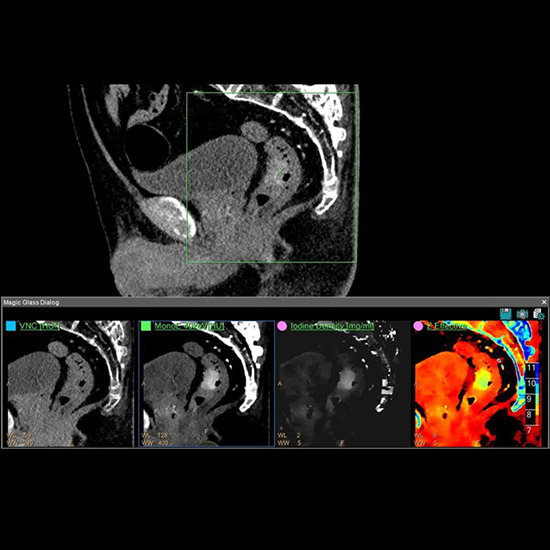

This powerful scanning diagnostic allows clinicians to characterize tumors with more certainty than current standard scanning. It acquires images at two different energy levels to provide a textured landscape that differentiates various elements in the body based on their material density or atomic numbers.

Black and white images from traditional Computed Tomography (CT) scans can be difficult to assess while Spectral CT provides a clearer picture. “It has shown great promise for non-invasive tumor characterization, for biopsy targeting by localizing ‘hot spots’ to improve therapy monitoring,” says Maya Barley, Head of Integrated Solutions and Roadmaps at Philips.

Spectral CT is poised to be the new generation of CT and provides medical teams with new horizons of diagnostic certainty.